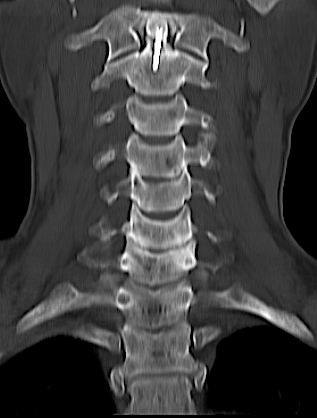

Reconstrucción coronal TC cervical 1 año.